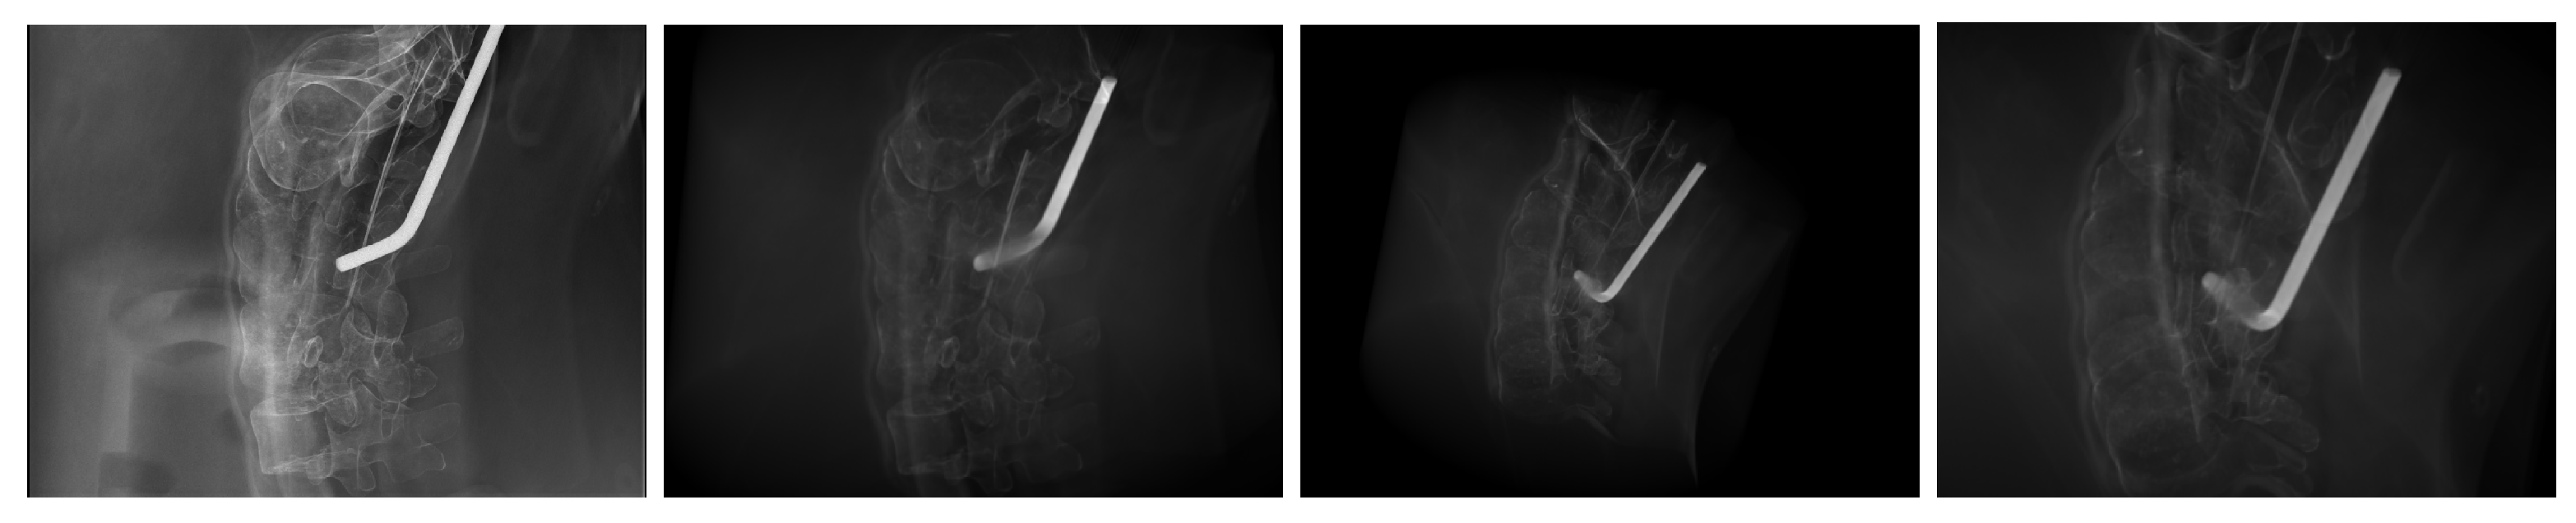

2.4. Image Data